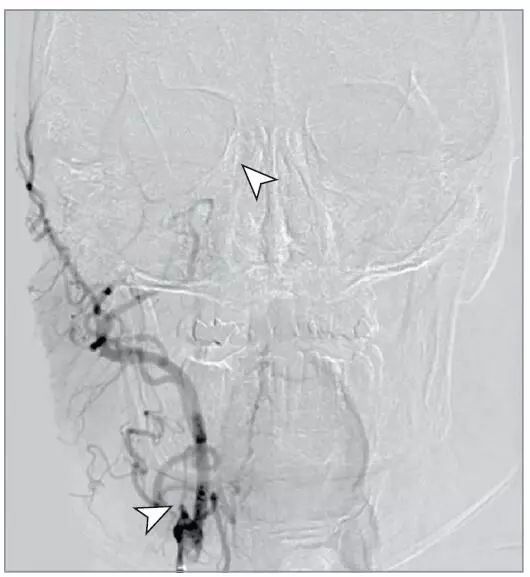

颈动脉夹层所致的眼科疾病:少见却紧急

病史摘要:59岁男性,突发右眼偏斜、同侧偏盲、左侧偏瘫就诊,有抽烟和慢性支气管炎病史。诊疗过程:血管造影示颈内动脉夹层合并颈内动脉终末闭塞和眼动脉损害。行血管成形术、颈内动脉支架置入术及颅内机械血栓切除术。术后出现眼部多种症状,眼底检查有黄斑水肿和缺血性视网膜症状,实验室检查无异常,CT和磁共振成像显示眼球突出情况。最终诊断为全眶梗死综合征。采用甘露醇和类固醇激素抗水肿治疗,出院三